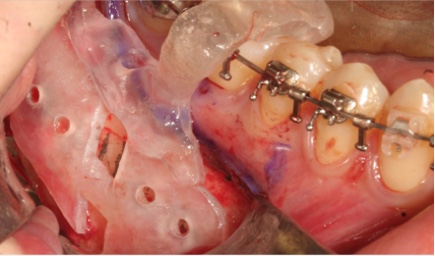

Saw Guides

- Customized for each patient to ensure precise bone incisions & deletions

FACEGIDE Plates

- Customized for each patient

- Reduced surgery time as no need to bend or cut customized plates